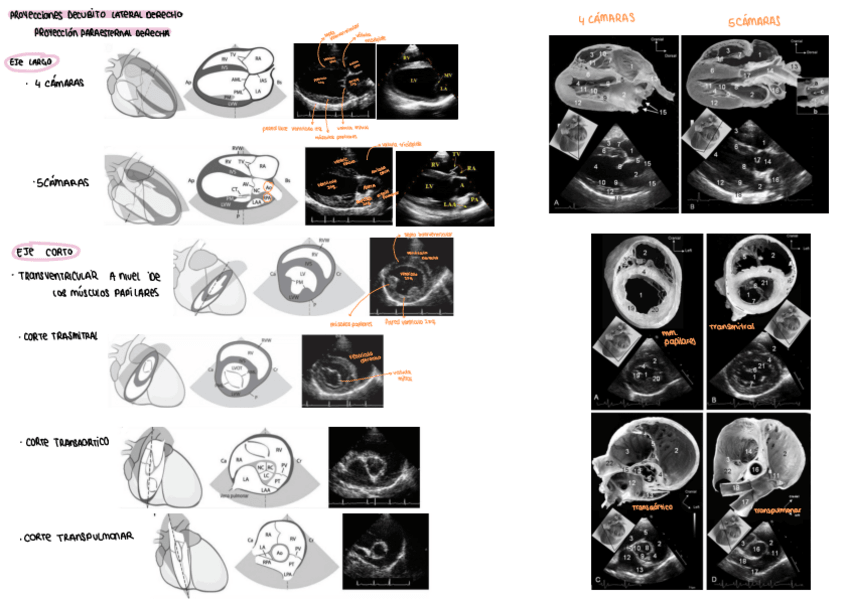

ecografía

He publicado nuevos apuntes de 3º Diagnóstico Por la Imagen: ecografía

Principios-basicos.pdf

ecocardiografia.pdf

Ecografia-abdominal.pdf